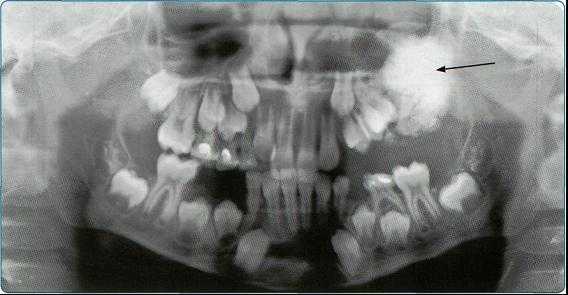

На основании панорамных снимков диагностируют кариес и его осложнения, кисты разных типов, новообразования, повреждения челюстных костей и зубов, воспалительные и системные поражения. У детей хорошо определяется состояние и положение зачатков зубов.

Особенно важно использовать ортопантомографию в детской стоматологии, где она не имеет конкурентов в связи с низкими дозами облучения и большим объемом получаемой информации. В детской практике ортопантомография помогает диагностировать переломы, опухоли, остеомиелит, кариес, периодонтиты, кисты, определять особенности прорезывания зубов и положение зачатков.